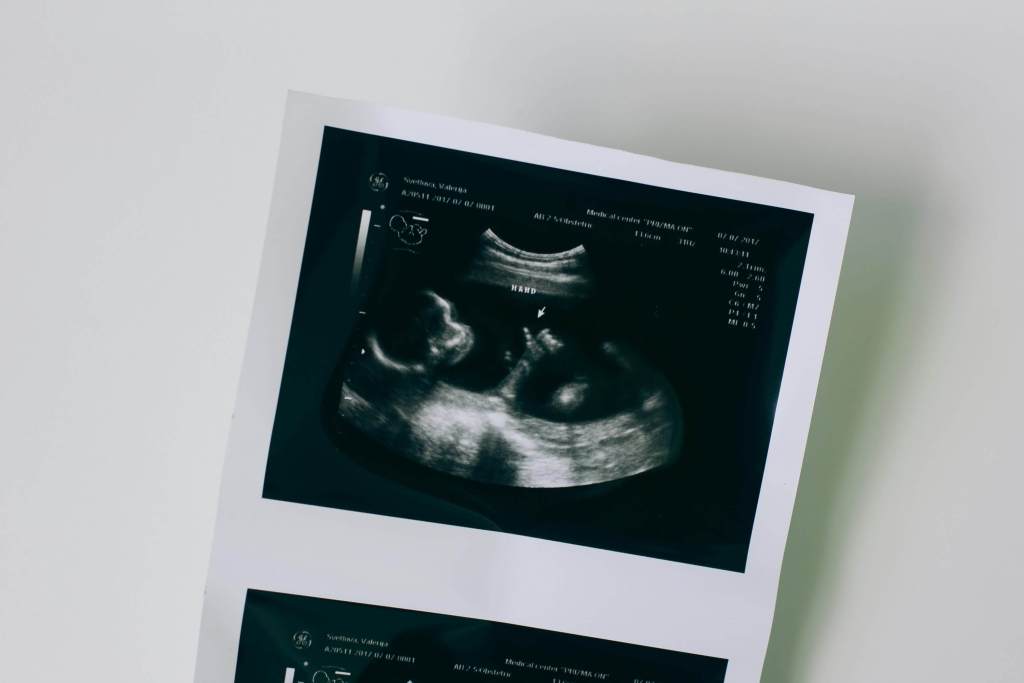

La detección de los primeros latidos del corazón del feto, es posible gracias a las tecnologías modernas, como el ultrasonido. A través de un ultrasonido, los médicos pueden observar el latido cardíaco y confirmar que el embarazo está evolucionando normalmente. Este primer latido no solo es un signo de vida, sino también una indicación de que el corazón del bebé está comenzando a funcionar correctamente. Para los futuros padres, escuchar el latido del corazón de su hijo por primera vez es un momento emotivo e inolvidable, que fortalece el vínculo con el bebé en desarrollo.

El monitoreo de la frecuencia cardíaca fetal en esta etapa se realiza comúnmente a través de un ultrasonido. Esta herramienta permite a los médicos observar el latido del corazón y evaluar su ritmo y regularidad. La información obtenida es crucial para determinar si el feto se está desarrollando adecuadamente y si hay alguna anomalía que requiera atención médica. Un ritmo cardíaco dentro del rango esperado es generalmente un buen indicador de que el embarazo está avanzando sin complicaciones.

El ultrasonido y la ecografía Doppler son dos métodos fundamentales para medir y evaluar la frecuencia cardíaca fetal durante el embarazo. Estos procedimientos permiten a los profesionales de la salud obtener una imagen clara del corazón del bebé y monitorear su ritmo cardíaco en tiempo real. El ultrasonido es una técnica no invasiva que utiliza ondas sonoras para crear imágenes del feto en el útero, proporcionando información valiosa sobre su desarrollo y bienestar.